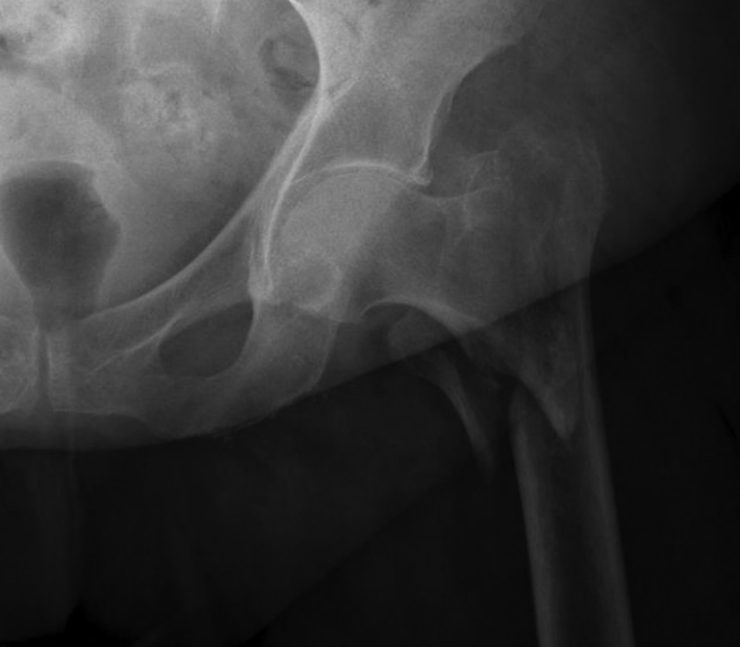

股骨头与股骨颈的血供解剖对评估股骨近端骨折后缺血性坏死风险至关重要(图2)。其主要血供来自旋股内侧动脉,近期研究也强调了臀下动脉的重要性。旋股内侧动脉起源于股深动脉和股总动脉,走行于梨状肌与髂腰肌之间,随后分为深支和降支。深支行经股方肌与闭孔外肌之间朝向股骨头,进入髋关节囊后部。进入关节内后,动脉分为后上滋养动脉,此为股骨头颈最重要的血供来源。近期对臀下动脉的研究显示,它为股骨头提供了重要血供,在某些解剖变异中甚至是优势血供来源。臀下动脉的远侧深支在进入髋关节囊后下部前与旋股内侧动脉吻合。其他血管如旋股外侧动脉、臀上动脉、闭孔动脉及位于股骨头圆韧带内的闭孔动脉髋臼支,对股骨头血供贡献较小。

图2. 股骨近端血管解剖。股骨头的主要血液供应来自旋股内侧动脉,该动脉在穿入关节囊形成其终末支持带分支前向后上方走行。